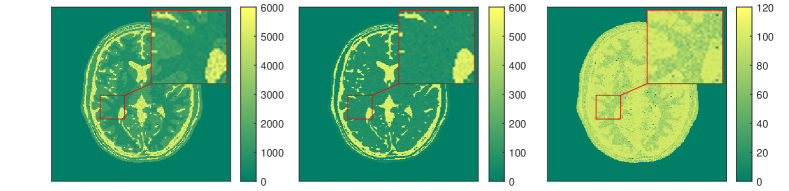

In [178] a line-search strategy is proposed to find the step size-parameter that has to be adjusted in dependence of the unknown Lipschitz constant of in order to guarantee a sufficient descent of the objective in each step of the algorithm. The overall method alternates between the three optimization steps and is shown to converge against a limiting-stationary point. Prototypical numerical results from [178] are depicted in Figure 9, where the dictionary learning approach is compared against the pure Levenberg-Marquardt method from Section (2.2) and the BLIP method in [52]. Here the number of image frames was chosen to be and the under-sampling factor is 16. Moreover small complex noise was added to the under sampled Fourier data. The details can be found in [178] where also extensions of the methods are discussed.